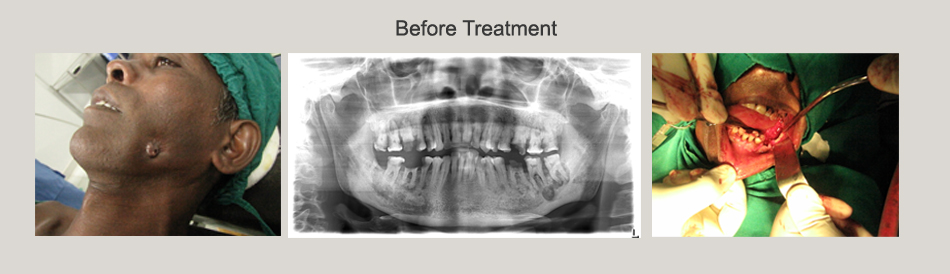

Osteoradionecrosis